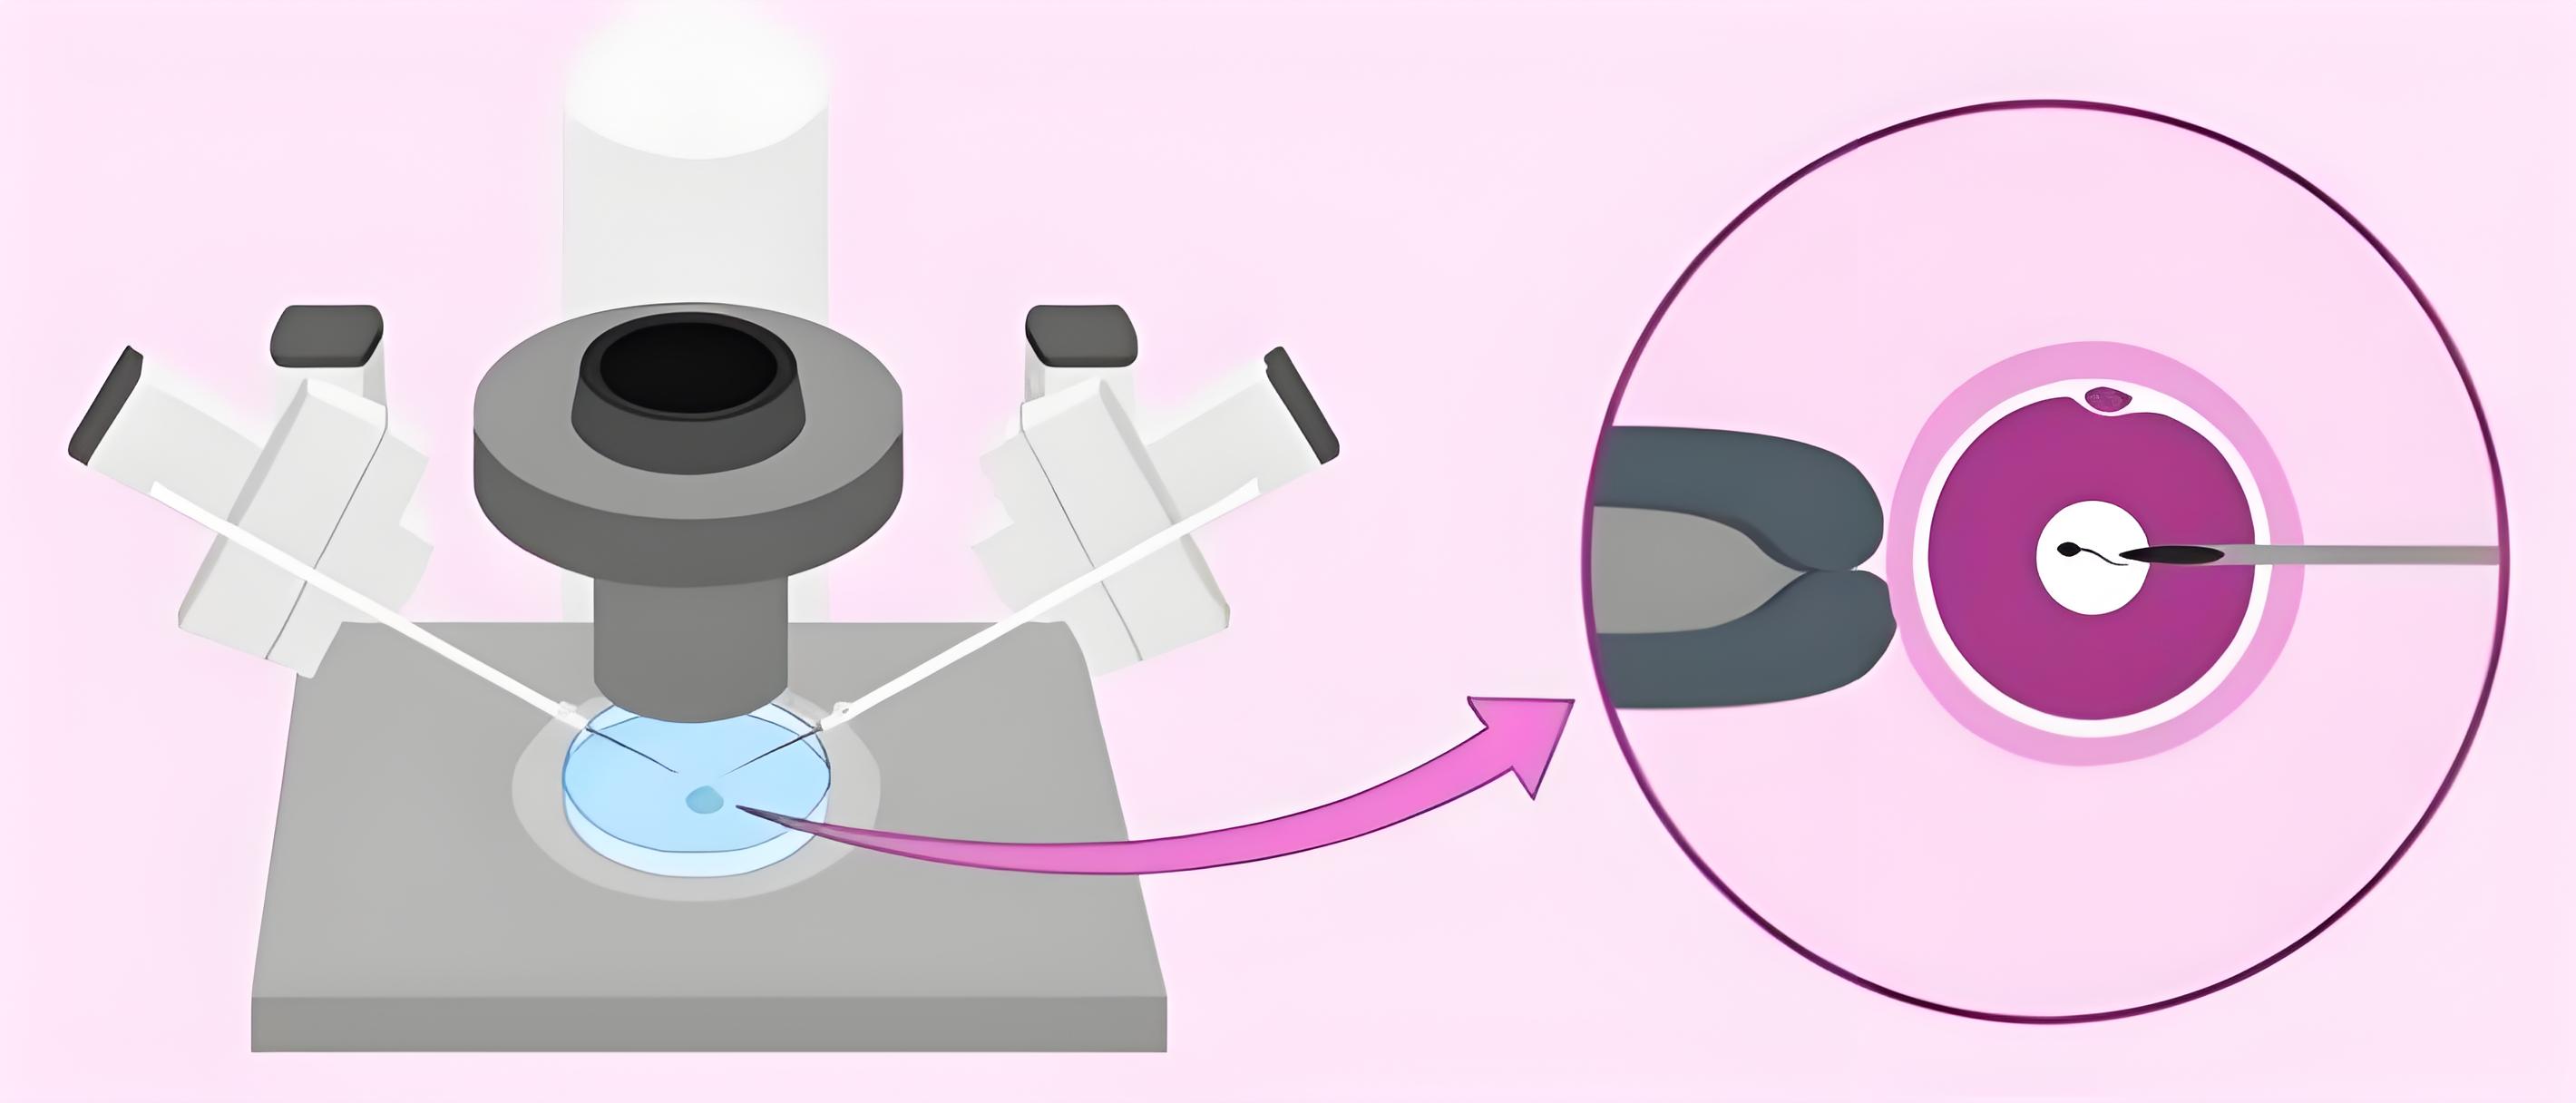

3、精卵结合

男性一般通过手淫法完成取精。完成取精后,专家会运用全新的Perecoll梯度离心精子洗涤技术对提取的精液进行洗涤和优化,去除死精、炎症细胞、精子抗体、碎片率高及活力低的精子,再通过高倍显微镜从中挑选出形态正常、活性强的优质精子。之后,HRC专家会借助显微操作系统将经洗涤优选过的精子直接注射到卵子内,使其跨越精子运动等一系列步骤,实现高达99%的卵子受精率。